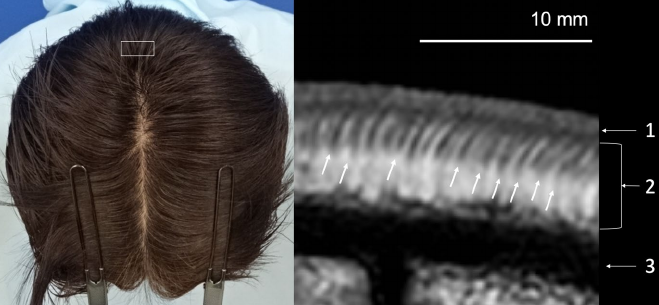

모발이식은 아주 얇고 작은 모낭과 거기 붙어있는 머리카락을 다루는 수술입니다. 모발의 굵기를 이야기할 때 쓰는 마이크로미터(㎛) 단위는 우리가 익숙한 센티미터로 바꾸게 되면 0.0001cm에 해당합니다. 이런 작은 조직을 다루는데 육안으로 하는 것보다는 고배율의 확대를 통해 시야를 확보하고 수술을 진행하는 것이 훨씬 좋은 결과를 가지고 오는 것은 자명합니다. 모발이식은 성형외과 수술분야의 하나인 미세수술(micro-surgery)로 분류할 수 있습니다.

정밀한 조작으로 모낭을 다루어야 좋은 결과를 얻을 수 있기 때문에 좋은 확대능을 가진 장비를 쓰는 것은 좋은 결과를 만들기 위한 핵심요소라고 볼 수 있습니다. 현미경 사용 시 20% 이상의 효과개선이 있다는 것이 이미 많은 실험 및 논문으로 발표되었습니다.

씨거(Seager)는 같은 두피 면적내에서 채취한 모발의 양이 현미경 사용 시 20%가 증가한다는 내용을, 번스타인(Bernstein)은 확대경(loupes)를 사용한 것에 비해 현미경 분리(microscopic dissection)이 17% 더 많은 모발을 획득하였다고 기술하고 있습니다.